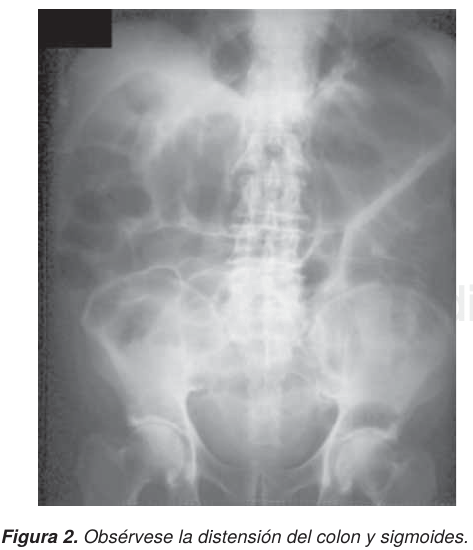

DIAGNÓSTICO

El diagnóstico del síndrome de Ogilvie debe sospecharse en pacientes hospitalizados, con o sin cirugía previa o con alguna de las múltiples entidades a las que se asocia. La radiografía simple de abdomen (Figura 2); es el estudio de gabinete esencial para el diagnóstico, la cual muestra como característica una dilatación-distensión gaseosa masiva del colon hasta el ángulo esplénico, distensión moderada del intestino delgado, ausencia de niveles y edema en la pared. El enema baritado a baja presión permite junto con la colonoscopia determinar la ausencia de lesión en la luz del colon. Si el cuadro clínico es de presentación paulatina (3 a 7 días), se pueden para tomar radiografías simples seriadas de abdomen para valorar el posible aumento de volumen del colon derecho. Las técnicas de la colonoscopia para el diagnóstico y tratamiento han sido modificadas de acuerdo a los casos. La tomografía axial computada (TAC), recurso de imagen más detallado para el diagnóstico, y la radiología intervencionista han revolucionado el tratamiento médico para el SO, sin recurrir a la cirugía, aunque ésta se tenga que realizar sobre todo en los casos complicados o recidivantes.